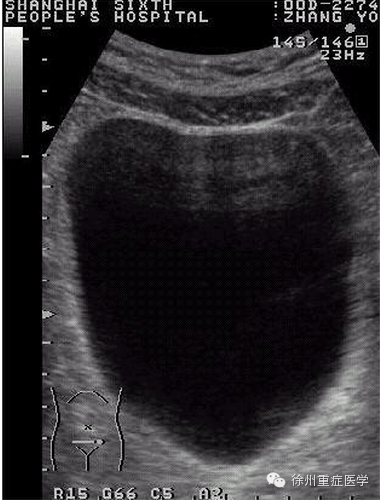

振子发射超声大部分以0°角发射(主瓣),少数出现偏斜放心发射,即旁瓣(side lobe)。(图1)超声在形成图像时默认为回声均来自于0°方向的回声。声束宽度伪像可以通过调整声束形状进行识别。声束的近场宽度和探头尺寸相似,最窄处出现在焦点,偏斜扩大的部位出现在远场。远场声束的宽度可以超过探头的尺寸。当位于旁瓣区的强回声,因与焦点位置的不同而产生不同的图像(如图2)。旁瓣为低能量、放射状包绕主瓣周边的声束。它的能量多来源于径向排列的压电晶体,因此多见于线性阵列探头。当位于旁瓣的强反射源时,回声会被错误是认为来自于主瓣。如图3。作为一种声束宽相关的伪像,腹部探测时,腹壁的筋膜和肌层都是平整的界面,常出现混响伪像,出现在声像图的浅表部位,尤其在胆囊和膀胱等液性器官的前壁,更为明显(图3-2

3-2 膀胱前壁混响,可通过调节时间增益减少或消除伪像。